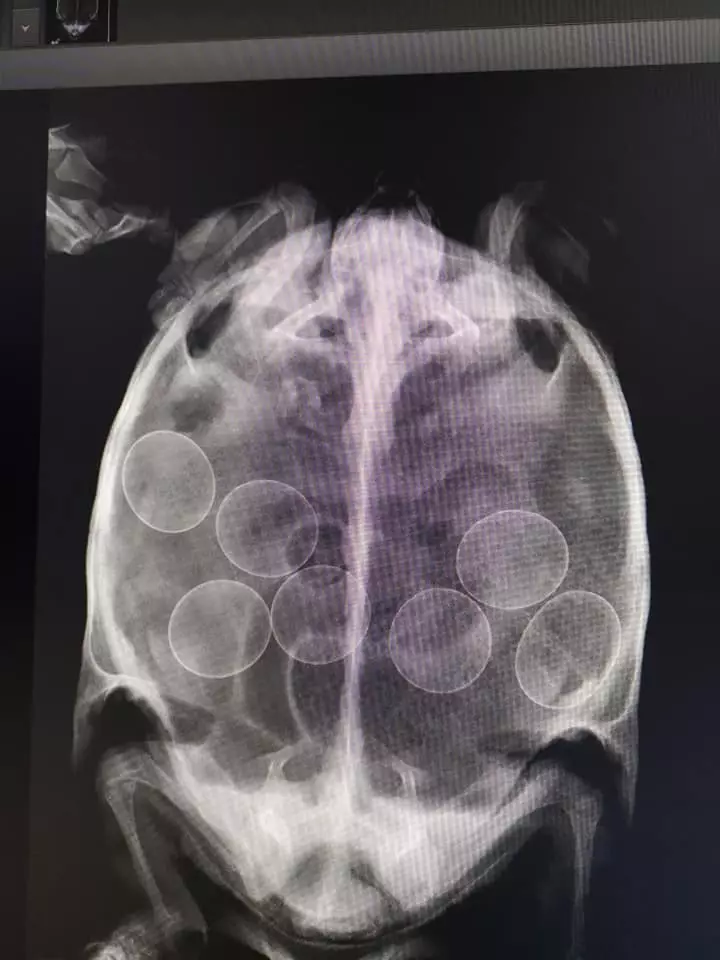

Ker naši pacienti ne morejo govoriti se pri pregledih in pred postavitvijo diagnoze odločimo za odvzem krvi ali drugih telesnih tekočin in naredimo rentgen ali ultrazvok.